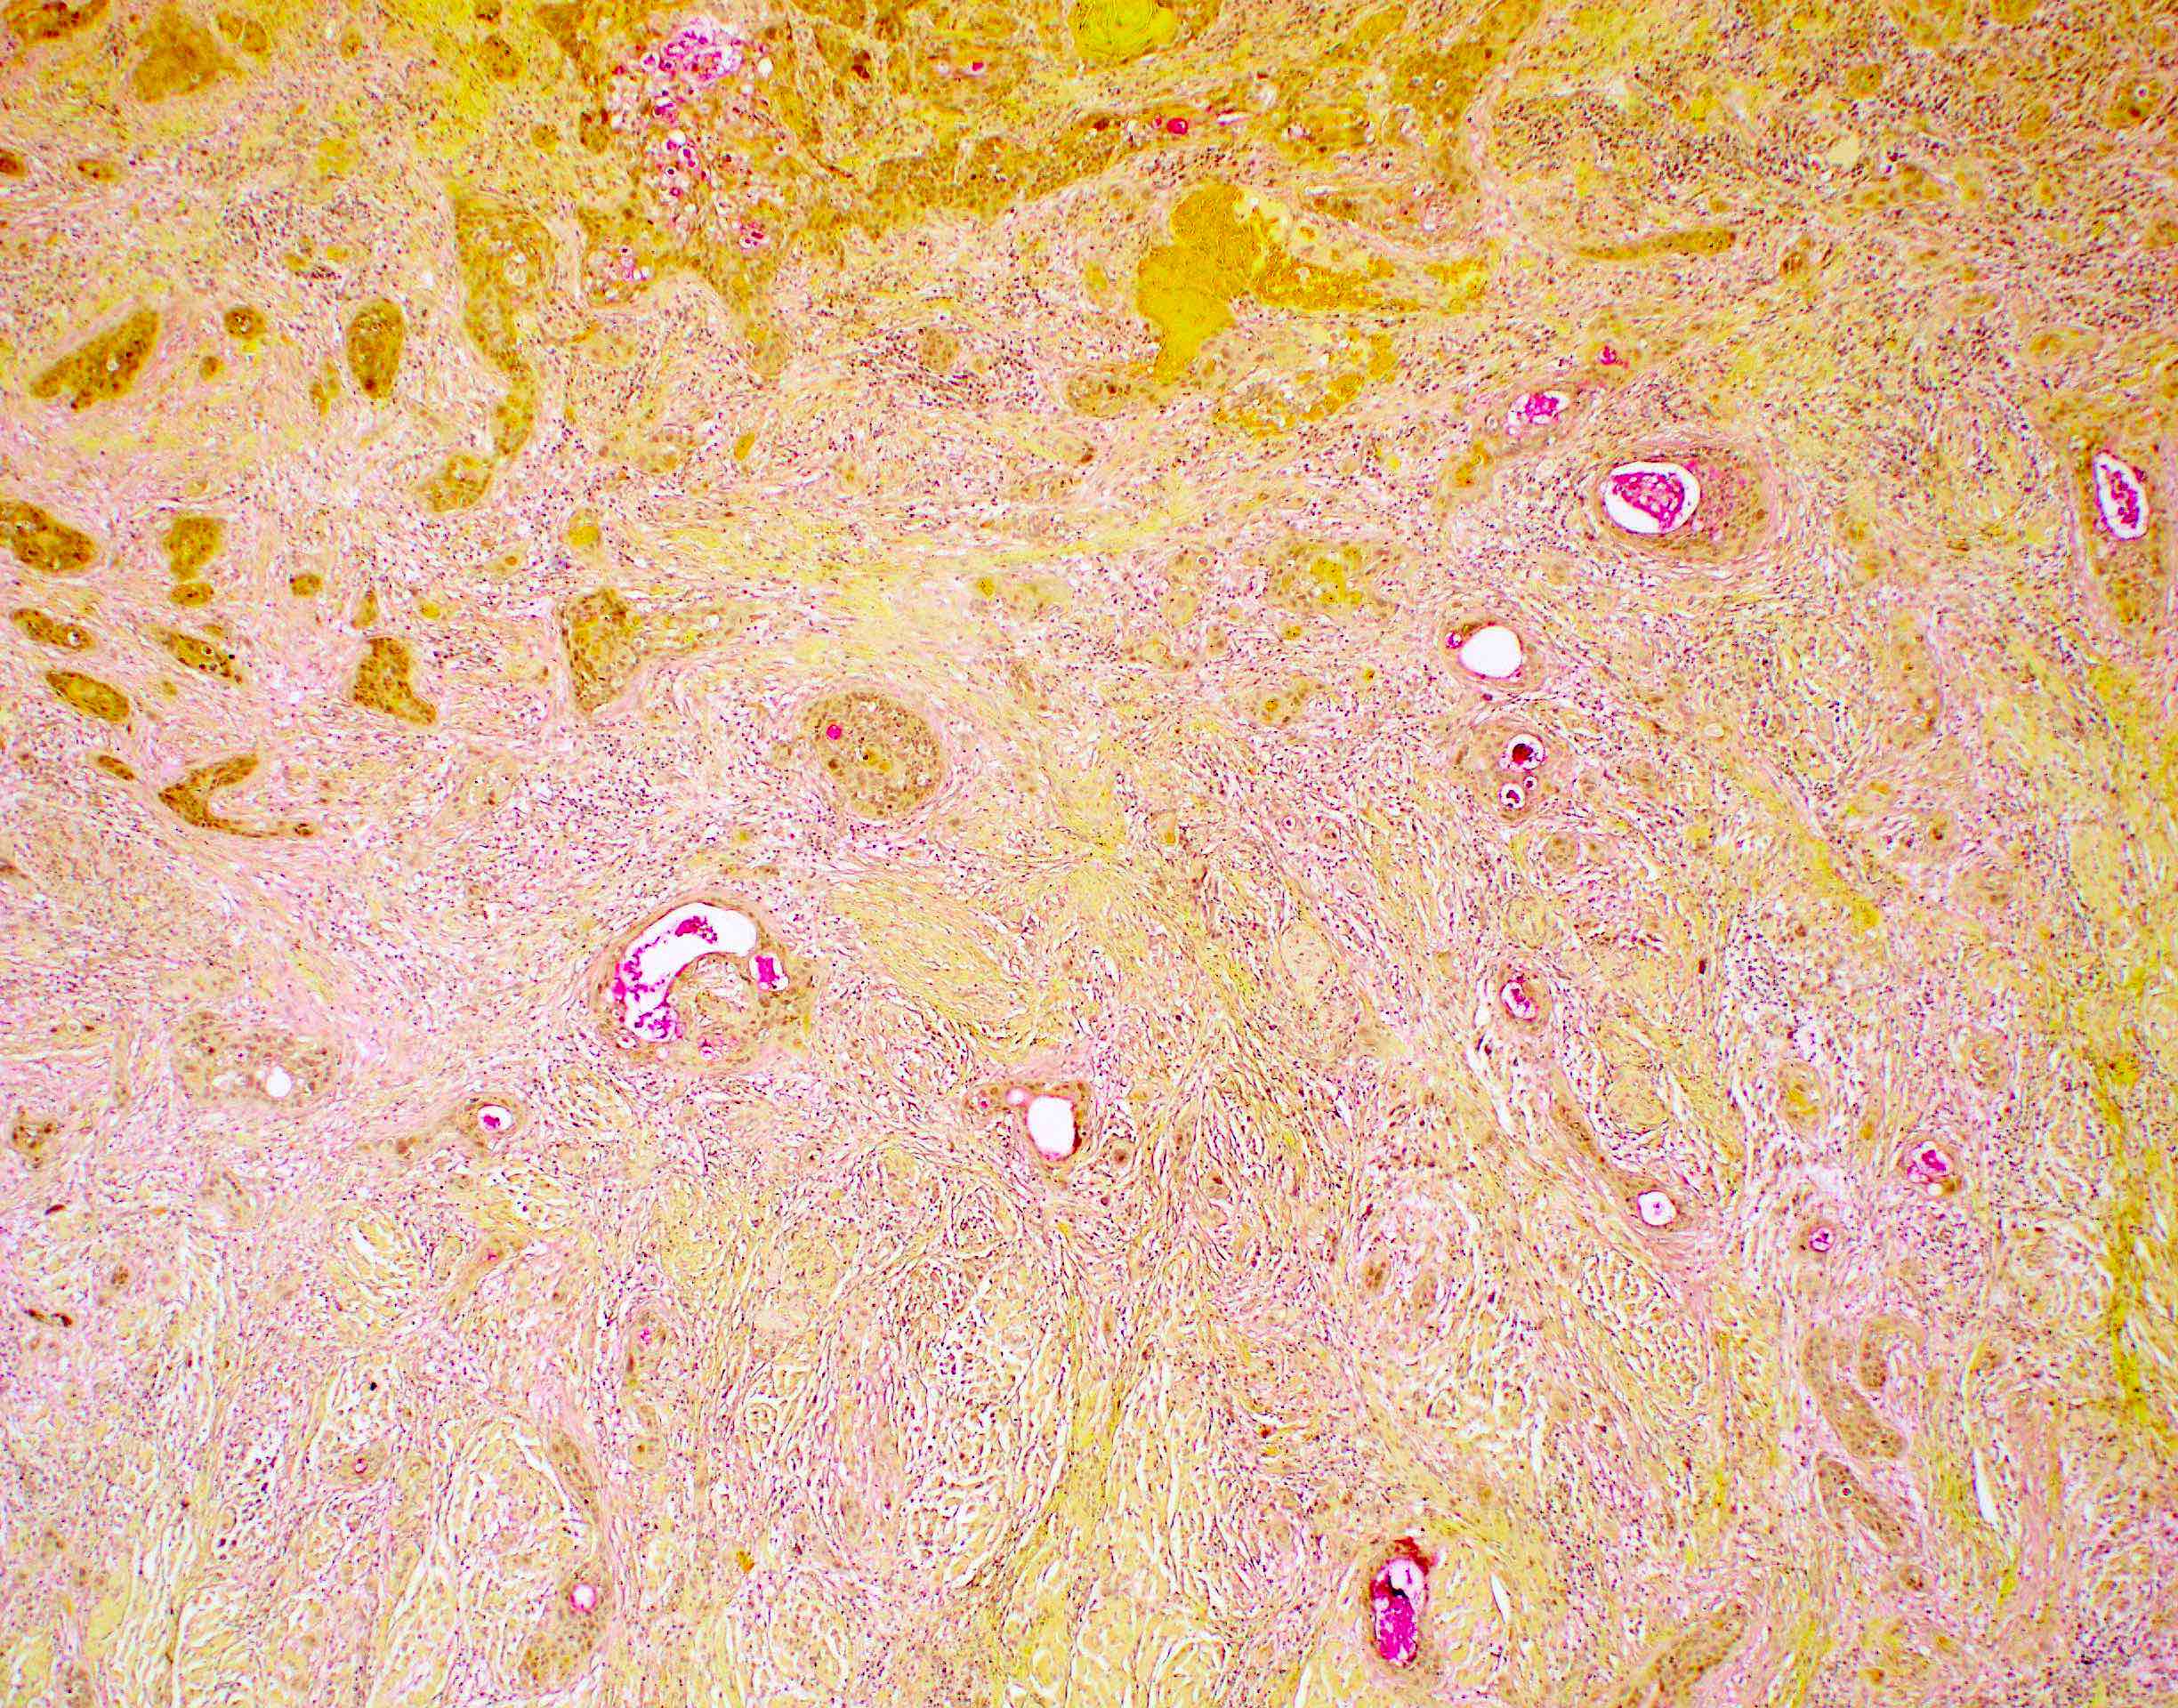

- Spindle cell / sarcomatoid squamous cell carcinoma (Am J Otolaryngol 2008;29:123)

- Most commonly occurs postradiotherapy or as second primary

- Mesenchymal in appearance

- Atypical plump spindled cells arranged in fascicles or storiform pattern

- May have metaplastic or neoplastic cartilage or bone

Microscopic (histologic) images

Contributed by Ruta Gupta, M.B.B.S., M.D.